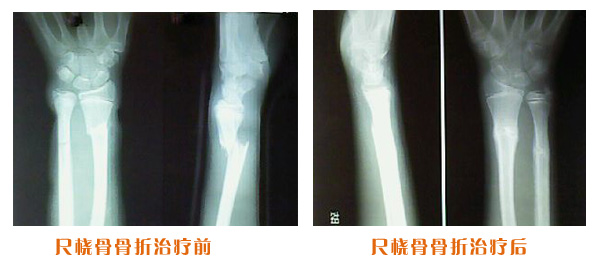

肥城市安駕莊梁氏骨科醫(yī)院是一所以梁氏手法正骨配合膏藥為特色的現(xiàn)代化??漆t(yī)院。

梁氏骨科術(shù)始創(chuàng)于清雍正年間,歷經(jīng)八代,至今已有三百年歷史。據(jù)1929年泰安縣志載“梁瑞圖先生,字增生,號(hào)蓮峰,安駕莊人,精岐黃并發(fā)明接骨,凡跌打車凡跌打車軋皮不破而碎骨者......【詳細(xì)】 |